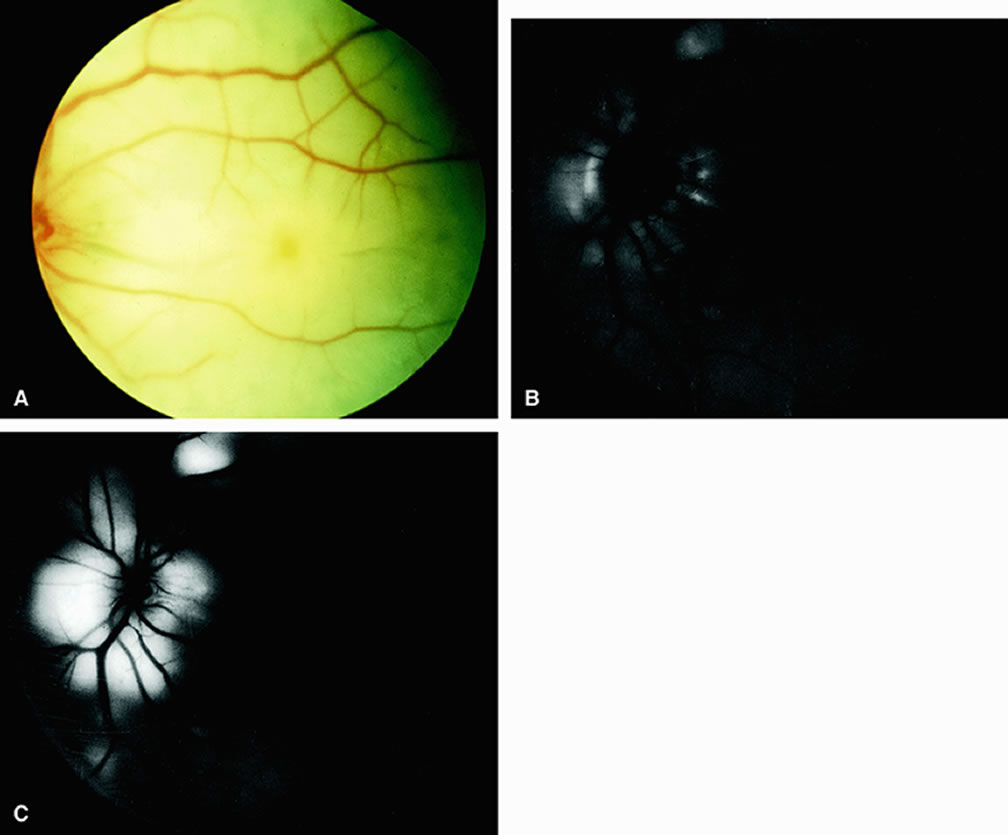

Normally, the choriocapillaris is completely filled with fluorescein dye within 5 seconds after the first appearance of dye within it. In eyes with the ocular ischemic syndrome, this filling can be delayed in extreme cases for 1 minute or longer. The posterior choroid is supplied by the temporal and nasal posterior ciliary arteries.2 In some normal eyes, but particularly in eyes with the ocular ischemic syndrome, delayed, asymmetric filling of the areas supplied by these vessels can be seen (Fig. 1). Filling of the retinal arteries is often also delayed in eyes with the ocular ischemic syndrome, and this manifests as a delayed arm-to-retina circulation time. Although the retinal arteries usually start to fill within 15 seconds after an antecubital intravenous injection of sodium fluorescein dye, this time range varies according to several factors, including the site of injection, the rate of injection, and body circulation. A visible leading edge of dye (see Fig. 1) within a retinal artery is almost always abnormal after an intravenous injection and indicates diminished flow. In the Retina Vascular Unit at Wills Eye Hospital, Philadelphia, the upper-normal limit for retinal arteriovenous transit time (time from the first appearance of dye in the temporal retinal arteries of the arcades to the time when the corresponding veins are completely filled) is considered to be 10 to 11 seconds. The retinal arteriovenous transit time is usually prolonged in eyes with the ocular ischemic syndrome; in fact, this prolongation of time is the most common fluorescein angiographic feature in eyes with the ocular ischemic syndrome. Leakage of fluorescein dye from the retinal vessels, particularly the arteries, occurs in 85% of eyes with the ocular ischemic syndrome (Fig. 2). Presumably, hypoxia and subsequent endothelial cell damage cause this leakage of dye. Leakage of fluorescein dye from the retinal vessels can be seen in the posterior pole and periphery. This hyperpermeability, combined with leakage of serum from microaneurysmal abnormalities, appears to account for the macular edema observed in some eyes with the ocular ischemic syndrome (see Fig. 2). Leakage of fluorescein dye from neovascularization of the disc is seen in approximately one third of eyes with the ocular ischemic syndrome (see Fig. 2). Hyperfluorescence resulting from leaking neovascularization of the retina is less common. Retinal capillary nonperfusion is visible on fluorescein angiography in some cases. Ischemic optic neuropathy is rarely observed. Iris neovascularization is found in approximately two thirds of cases at the time the diagnosis is made. Fluorescein angiography is helpful in differentiating the ocular ischemic syndrome from conditions that can mimic it, including central retinal artery obstruction, mild central retinal vein obstruction, and diabetic retinopathy. Of these conditions, only the ocular ischemic syndrome has delayed choroidal filling present. Moreover, late staining of the retinal arteries is unusual with the other conditions. An increased arteriovenous transit time is usually present in eyes with the ocular ischemic syndrome but can also be seen in eyes with central retinal artery or vein obstruction and eyes with diabetic retinopathy and nonperfusion of the retinal capillary bed. OPHTHALMIC ARTERY OBSTRUCTION Clinically, acute ophthalmic artery obstructions differ from acute central retinal artery obstructions in that persons with the former often have no light perception and the retinal whitening appears more intense on examination.3 A cherry-red spot is often absent in eyes with acute ophthalmic artery obstruction, but its presence does not rule out the diagnosis (Fig. 3A). Electroretinography often reveals diminished amplitudes of both b- and a-waves that are caused by inner and outer retinal ischemia, respectively.3 In contrast, with a central retinal artery obstruction alone, the a-wave amplitude is usually normal and the b-wave amplitude is often diminished because of inner retinal ischemia.4 Fluorescein angiography of eyes with acute ophthalmic artery obstruction shows delayed filling of the retinal vessels and usually the choroidal vessels as well (see Fig. 3B and C). Focal, pinpoint areas of staining resulting from leakage of dye at the level of the retinal pigment epithelium can be seen in some instances. Diffuse staining is also occasionally observed. Prominent staining of the retinal vessels is usually absent with acute ophthalmic artery obstruction, although it can be seen with chronic ophthalmic artery obstruction. RETINAL ARTERY OBSTRUCTION With acute central retinal artery obstruction, filling of the choroid is usually normal. Filling of the retinal arteries is often delayed, and in severe cases, a leading edge of dye can be seen (Fig. 4). A delay in retinal arteriovenous transit time is often noted.5 Box-carring or segmentation of the dye column can be seen in both the retinal arteries and veins when the obstruction is marked. In some cases, the flow appears normal because reperfusion of the blocked artery can occur fairly rapidly.6 Intraretinal leakage of dye in the late phases of the study, in a pattern consistent with macular edema, is generally not seen in eyes with acute central retinal artery obstruction. Fluorescein angiography can help identify eyes with acute central retinal artery obstruction in instances when the retinal whitening is subtle and the diagnosis is in question. Approximately 10% of eyes with acute central retinal artery obstruction have a cilioretinal artery that supplies the retina in the papillomacular bundle and extends into the foveola.7 In more than 80% of these eyes, the visual acuity eventually improves to 20/50 or better. Fluorescein angiography typically shows earlier filling within the patent cilioretinal artery and the veins draining the area that it supplies compared with the filling of the remainder of the retina, which is supplied by the central retinal artery (Figs. 5 and 6). Fluorescein angiography of eyes with marked, acute branch retinal artery obstruction reveals a lack of filling of the retinal capillary bed within the distribution of the involved vessel. Retinal veins that normally drain the damaged area also demonstrate a delay in filling. With severe blockage, retrograde filling can be seen in the distal aspect of an obstructed branch retinal artery (Fig. 7). Cilioretinal artery obstruction is similar to branch retinal artery obstruction except that the former vessel usually emanates from the edge of the optic disc (Fig. 8). Cilioretinal artery obstructions can be seen as isolated fundus abnormalities or in association with central retinal vein obstruction or acute anterior ischemic optic neuropathy.8 Cotton-wool spots are small areas of superficial retinal whitening that usually develop secondary to obstruction of axoplasmic flow caused by areas of focal retinal ischemia.9 Fluorescein angiography in these cases usually demonstrates relative hypofluorescence in the early and middle phase of the study (Fig. 9). Late staining of the cotton-wool spot can occur. As shown in Table 2, the differential diagnosis of cotton-wool spots is extensive; however, cotton-wool spots are most commonly observed in the setting of diabetic retinopathy, hypertensive retinopathy, collagen vascular disease, or hematologic abnormalities.